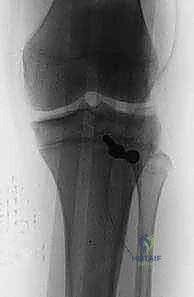

2. التصوير بالأشعة السينية (X-Rays)

هو الخطوة التشخيصية الأساسية. يتم أخذ صور من زوايا متعددة (أمامية خلفية AP، وجانبية Lateral). الصورة الجانبية هي الأكثر أهمية لأنها تظهر بوضوح مدى انفصال (انزياح) حدبة الظنبوب عن مكانها الطبيعي، وتظهر أيضاً ارتفاع الرضفة (Patella Alta).

5. التثبيت الداخلي (Internal Fixation)

هنا تبرز مهارة الجراح في اختيار طريقة التثبيت التي لا تضر بصفيحة النمو (إذا كانت لا تزال مفتوحة).

* استخدام البراغي المجوفة (Cannulated Screws): يتم إدخال سلك توجيهي رفيع أولاً، وبعد التأكد من موقعه بالأشعة السينية داخل غرفة العمليات، يتم إدخال برغي أو برغيين من التيتانيوم القوي فوق السلك لتثبيت العظم. يحرص الدكتور هطيف على توجيه البراغي من الأمام إلى الخلف، وفي بعض الأحيان بزاوية مائلة لتجنب اختراق صفيحة النمو قدر الإمكان.

بعد التأكد من قوة التثبيت عن طريق ثني وفرد ركبة المريض على طاولة العمليات، يتم غسل الجرح جيداً وإغلاقه في طبقات. تُوضع الساق في دعامة ركبة مفصلية (Hinged Knee Brace) مقفلة في وضع الاستقامة التامة لحماية الإصلاح الجراحي.